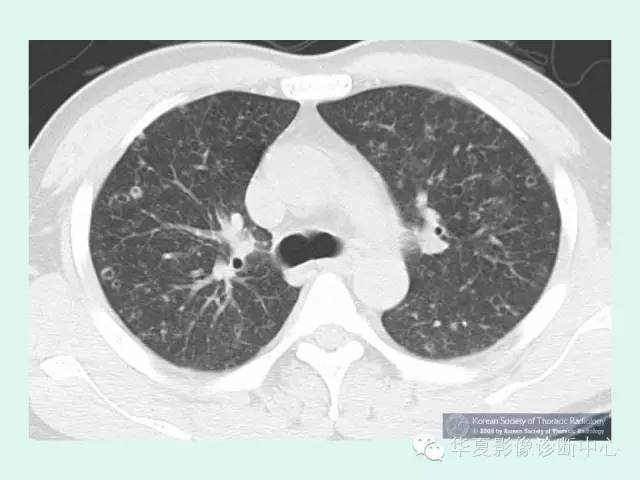

高分辨CT(HRCT)不仅对该病的鉴别诊断有意义,而且对判断该病的严重程度具有一定意义。病变通常分布在正常的肺组织中间,虽然在双下肺基底部位可以见到散在病变,但病变多位于上部,呈对称性均匀分布。早期病变主要以边界模糊的小结节阴影为主,有些病例可以见到有空洞形成。结节呈小叶中央性分布,并且伴有壁厚薄不等的囊性改变。随着病变的进展,囊性改变逐渐成为突出表现,这些囊腔大小差异很大,但通常直径小于1cm。囊腔可以为孤立样,也可互相融合,甚至形成肺气肿、气胸的表现。自发的出现小结节、空洞和囊性化是肺朗格汉斯组织细胞增生症较为特征性的改变。

1、双肺弥漫分布结节 是PLCH早期影像表现,直径约1~10mm大小,典型者直径1~5mm,病灶多两侧对称分布,中上肺野为主,肺基底部、肋膈角附近也可有少量分布。结节的数量可以是较少,也可以在肺野内弥漫分布不可数。结节边缘不规则为特征性地表现,结节周围为正常的肺组织围绕。

2、囊样病变 是PLCH的最常见的CT表现,通常直径小于10mm,但也可以达到20mm。囊样病变通常同结节并存,但是也可以是惟一的CT表现。囊样病变主要发生在肺上中野。可表现为圆形或卵圆形的囊变区.也可表现为各种各样的形状,囊样病变的壁可以很薄,仅仅可辨或者表现为厚壁和结节样。

3、晚期肺内纤维化 ,CT可表现为大小不等囊状影及纤维条索影,其囊状影形态呈圆形、类圆形,少部分囊状影亦可呈多边形、不规则形,囊壁薄而光整,囊壁<2mm,甚至部分囊壁在CT上观察不清,囊状影其直径一般<10mm以下,少数可大于10mm,可能与多个囊腔融合有关,随着囊状影的增多可出现蜂窝肺,此时可并发气胸,甚至反复出现,成为难治性气胸。